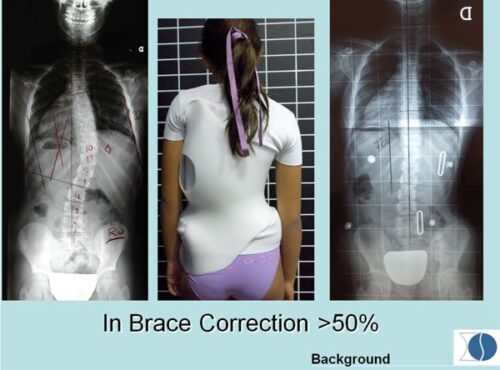

تهدف التقنية الجديدة إلى تحسين دقة تصميم الحزام الطبي بحيث يوزع القوى التصحيحية بدقة على مناطق الانحناء الفعلية. ولتحقيق ذلك، يتم اتباع عدة خطوات متتابعة:

المسح ثلاثي الأبعاد لجسم المريض: حيث يتم عمل مسح كامل للجذع لتحديد مناطق الانحراف بدقة عالية، وهذا يسمح بتخطيط أكثر دقة من الطرق التقليدية.

إنشاء نموذج افتراضي متناظر: يُستخدم هذا النموذج لعكس صورة الجذع بحيث تمثل النسخة المثالية للجسم، مما يسهل مقارنة الشكل المثالي بالجسم الفعلي.

مقارنة الصورة الأصلية بالنموذج الافتراضي: تُستخدم الخرائط اللونية لتوضيح المناطق التي يتجاوز فيها الانحراف 6 ملم، وبالتالي تحديد نقاط الضغط داخل الحزام بدقة.

تخصيص الحزام حسب حاجة كل مريض: يتم تصميم وسائد الضغط بناءً على التحليل الثلاثي الأبعاد، لضمان توجيه القوى التصحيحية نحو مناطق الانحناء الحقيقية، بدلاً من الاعتماد على التقدير البصري فقط.

المجموعة الأولى: استخدمت الحزام التقليدي (C.B.) الذي يعتمد على تحديد الوسائد يدويًا.

المجموعة الثانية: استخدمت الحزام الجديد (N.B.) المصمم وفقًا لقياسات ثلاثية الأبعاد.

2. تماثل الجذع وشكل الظهر

كانت الفروقات واضحة عند قياس تأثير الحزام على شكل الجسم:

الحزام الجديد حسّن شكل سطح الظهر بنسبة 49.6٪، وهو تحسن ملحوظ.

في المقابل، شهد مستخدمو الحزام التقليدي تدهورًا بنسبة 6.8٪ في شكل الظهر.

التماثل العام للجذع تحسن بنسبة 30٪ مع الحزام الجديد، بينما ازداد سوءًا بنسبة 2.2٪ لدى مستخدمي الحزام التقليدي.

وهذا يدل على أن استخدام القياسات ثلاثية الأبعاد يعزز التماثل العام للجسم بشكل واضح.